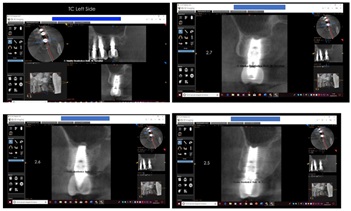

Control at six months on the right side and at 14 months on the left side, after finalization (Figure 27).

Figure 27: Control at six months on the right side and at 14 months on the left side.

Rx details in figure 28.

Figure 28: Left Side and Right Side note: the red arrows were the old sinus pavment and the yellow arrows, the new sinus pavment.

Control two months after loading on the right side and sixteen months on the left side (Figure 29).

Figure 29: Control two months after loading on the right side and sixteen months on the left side.